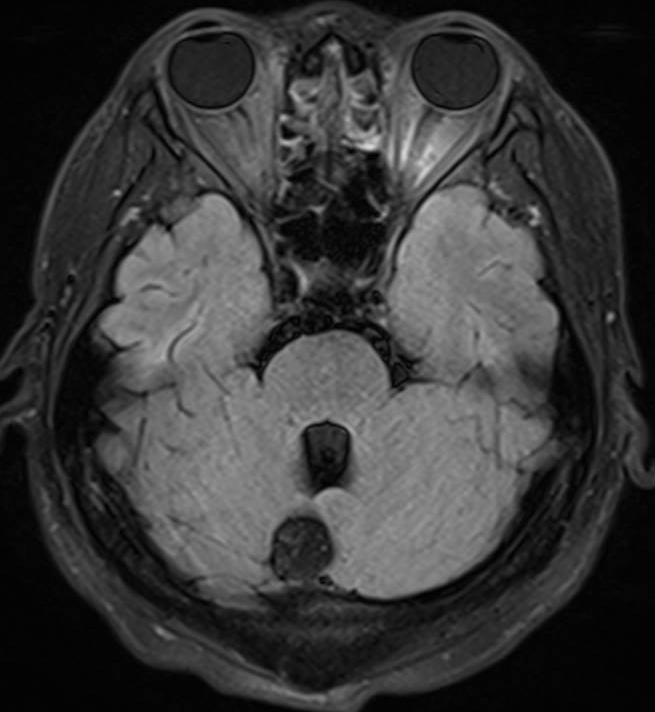

医生要求紧急做颅脑MRI,影像很快就传到了电脑上(图1-6)。医生解释,小脑蚓部占位考虑“脂肪瘤”,另有侧脑室旁白质脱髓鞘和左侧额顶叶皮质性脑炎的改变,“癫痫”可能为“继发性癫痫”。

图2 小脑蚓部占位T2

图3 小脑蚓部占位T2压水压脂